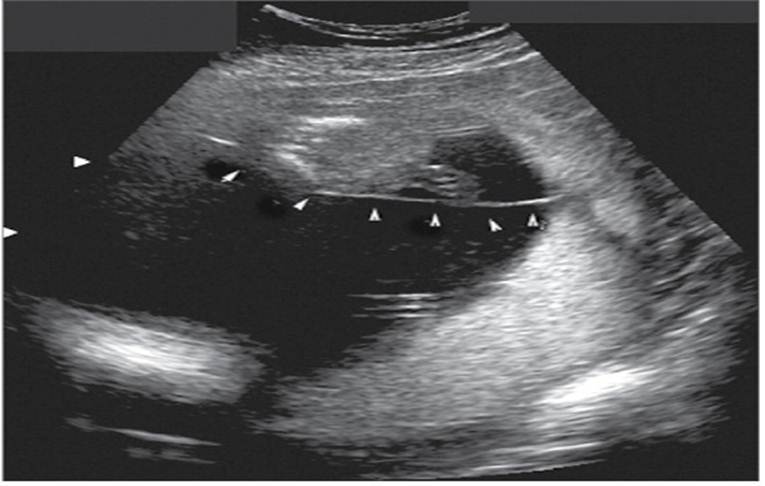

Measurement of incompetent cervix

Anterior uterine fibroid